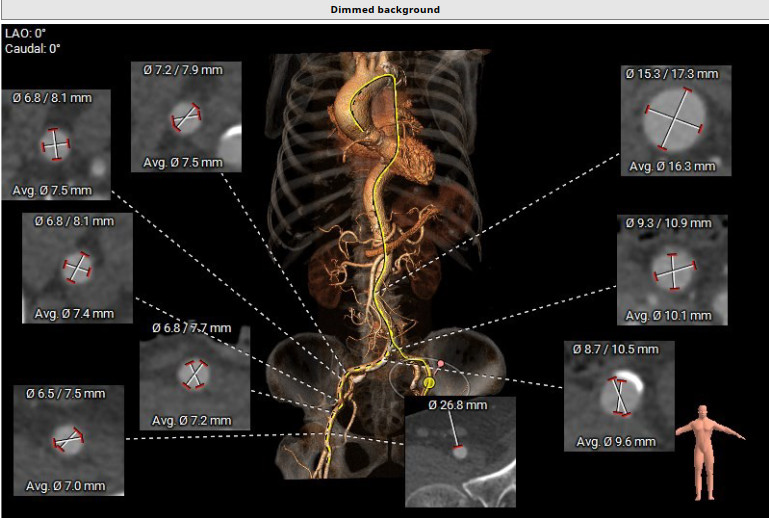

患者术前CT分析:主动脉瓣为三叶式,瓣叶增厚;主动脉弓角度偏小。

瓣环

窦部大小

左室流出道

升主动脉

瓣叶开放3D图

外周血管